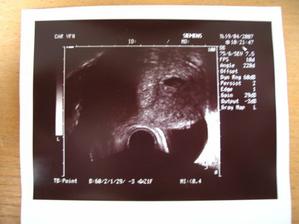

Dne 3.4.2007 to vypadá dle testů, že to vyšlo a my se snad dočkáme našeho vytouženého miminka a já nikdy nezapomenu děkovat a vážit si práce všeho personálu CAR u Apolináře. Dne 19.4.2007 nám bylo v CAR ultrazvukem potvrzeno, že opravdu čekáme naše vytoužené miminko. Dne 4.6.2007 jsme byli na genetickém UTZ ve 12+4.tt a UTZ dopadl na 1*. Dnes 26.7.2007 jsme byli na 3. ultrazvuku, jsme ve 20+2.tt a miminko je v naprostém pořádku. S maminkou už je to horši, ale snad všechno nakonec dobře dopadne. Dne 30.8.2007 jsme byli neplánovaně na 4. ultrazvuku a monitoru, protože maminka upadla na schodech, naštěstí je miminko v pořádku a neutrpělo žádnou újmu. Dnes 9.9.2007 jsme byli s tatínkem na 4D ultrazvuku v Gennetu Praha, máme krásné fotečky a DVD. Dozvěděli jsme se, že miminko v mém bříšku je holčička. Večer 9.9.2007 jsme naší holčičce vybrali jméno, je to Verunka.